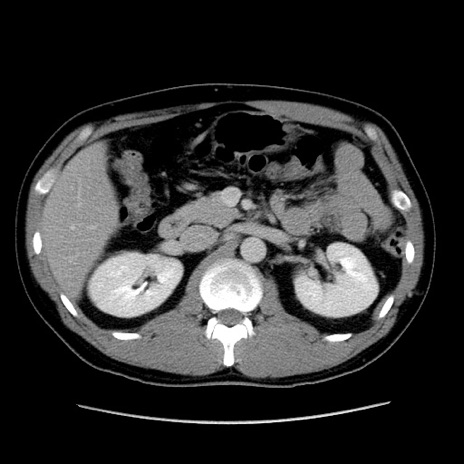

症例4(横断像)

【症例】30歳代男性

【主訴】腹痛、嘔吐

【現病歴】昨晩から突然の腹痛あり、その後嘔吐、軟便も出現。腹痛が改善しないため救急搬送となる。2日前にしめ鯖の食事歴あり。

【身体所見】意識清明、苦悶様、BP 135/90mmHg、BT 35.7℃、腹部:平坦、やや硬、心窩部〜臍部に自発痛、圧痛あり、筋性防御+、反跳痛-

【データ】WBC 8100、CRP 0.57